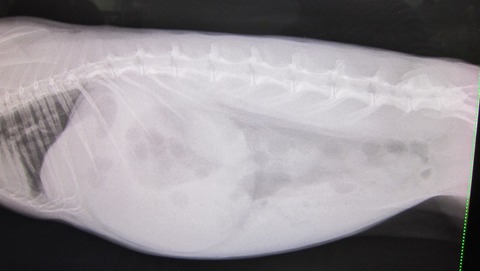

9日の譲渡会、

とてもよく食べ、なでなでアピール頑張ってたかぐらちゃん

排泄物もお見事でした

(赤丸は異変発見すぐに撤収した排泄物)

1つだけやけど出た

その後、牧草もぐもぐから始まっての…

出だした出だした

…週末の譲渡会、メンバー変更か?て若干考えたんですが

尾を引くこともなかったので予定通り参戦、